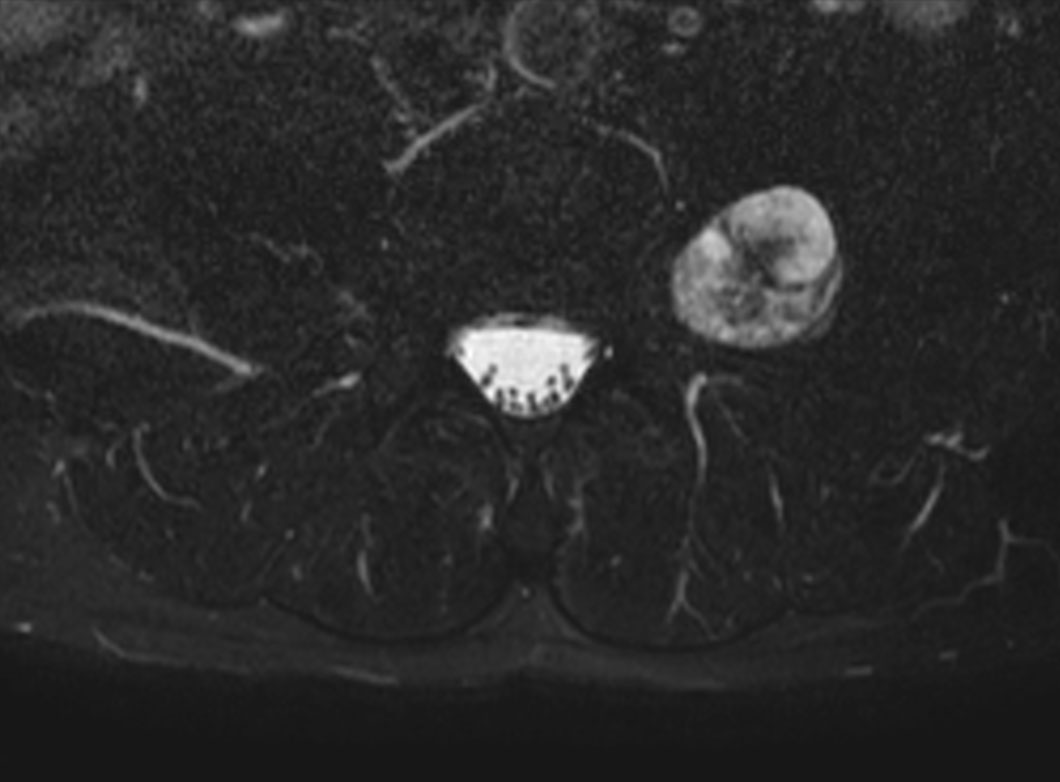

Neurography schwannoma (Compressed SENSE)

Patient with a lumbar neurography schwannoma.